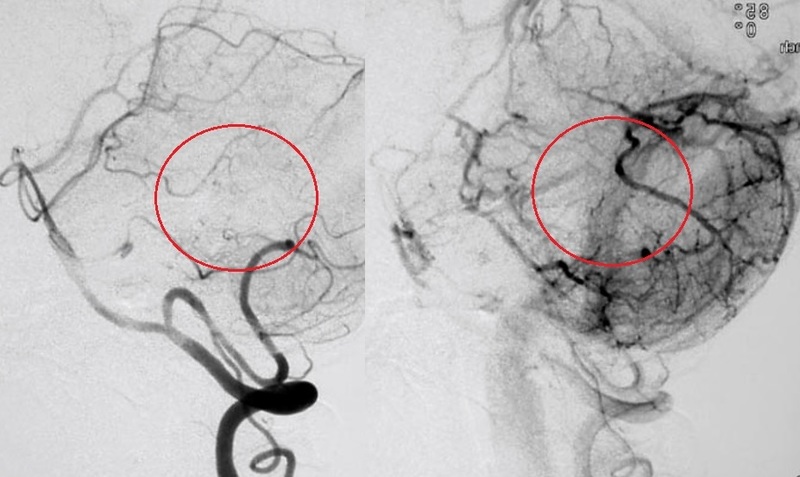

第一子出産から1ヶ月後に小脳のAVMの破裂により突然の激しい頭痛とめまいが起こり受診しました。マイクロカテーテルを流入動脈(ナイダスへ入る動脈)の末梢まで挿入し、NBCAとオイドラギット(Onyx類似の薬剤)を注入しAVMを完全に閉塞しました。その後再発なく7年が経過しています。